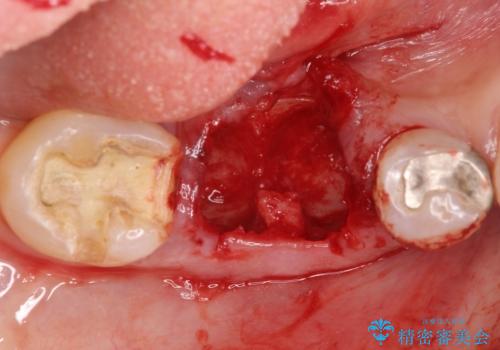

保存できない状態でしたので抜歯をして歯槽堤保存術を行いました。その後大臼歯部にインプラント治療を行いました。

欠損部に1本だけインプラントを埋入しても大きな被せ物になってしまい清掃性が悪くなるので清掃性が良くなるように2本小臼歯用のインプラントを埋入しました。

- 抜歯、歯槽堤保存術・11万円 インプラント体、アバット、仮歯、ジルコニアクラウン・42.9万円×2 骨造成・5.5万円 e-maxインレー・7.7万円 費用は治療当時の料金となります